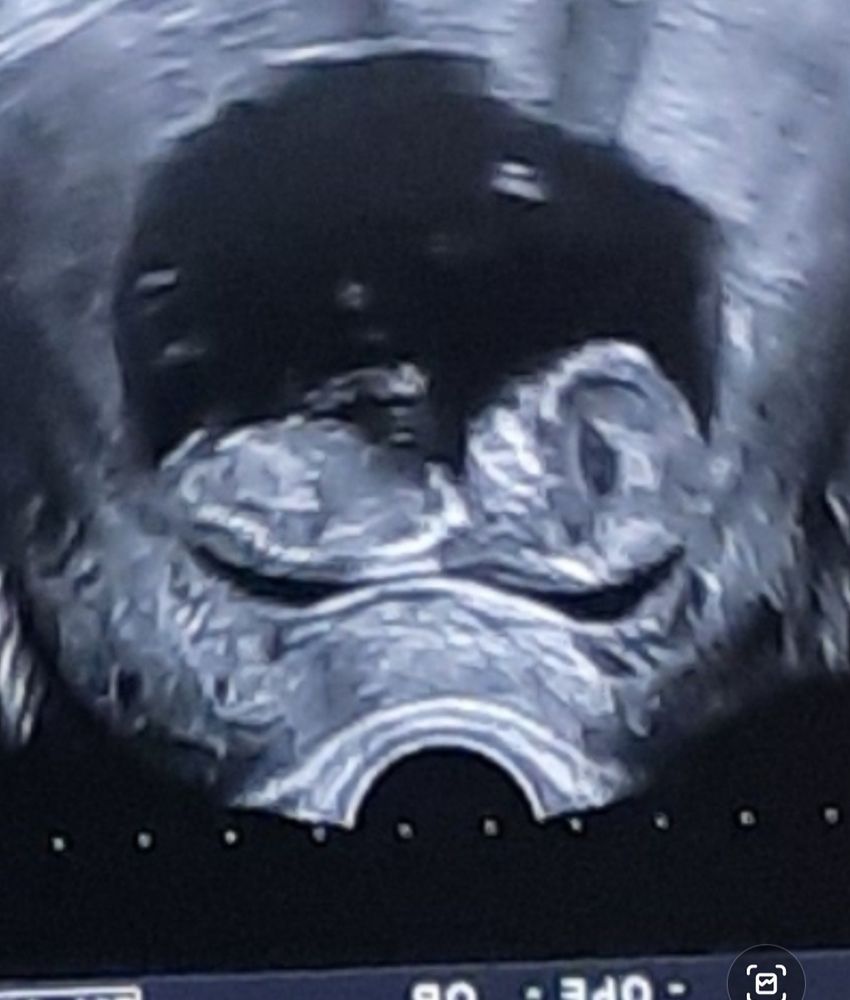

УЗИ 12,5 неделек

Качество плохое. У нас на фото четко торчит половой бугорок вверх под углом 90 градусов относительно позвоночника. Врач сразу сказала, что мальчик - писюлька торчит без наклона). У вас вообще не видно этого бугорка. Либо это девочка, и бугорок уже начал сглаживаться в половые губы, либо ракурс плохой